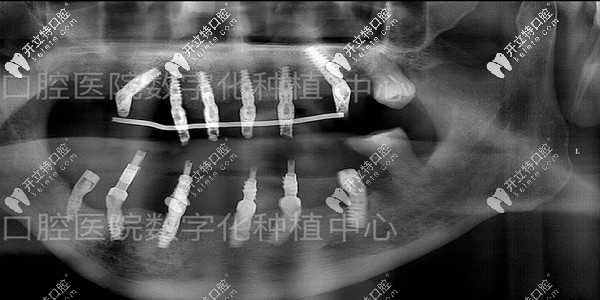

種牙后的口腔檢查